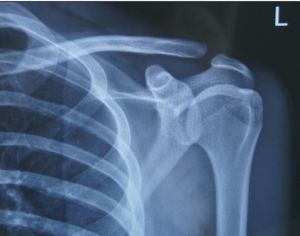

肩鎖關節脫位X線檢查 X線檢查可以顯示出肩鎖關節的半脫位或真性脫位,必須與對側的肩鎖關節相比較,必要時可在應力下攝片,病人手握4—6kg重物下攝片,此時鎖骨外側端移位情況更為清楚。

X線檢查X線檢查可以顯示出肩鎖關節的半脫位或真性脫位,必須與對側的肩鎖關節相比較,必要時可在應力下攝片,病人手握4—6kg重物下攝片,此時鎖骨外側端移位情況更為清楚。